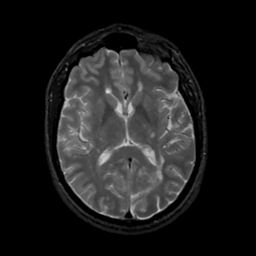

MR Study #16, June 23, 1991 -- Slice #27

[Home][Help][Clinical][Tour 1][Tour 2] Slice 27